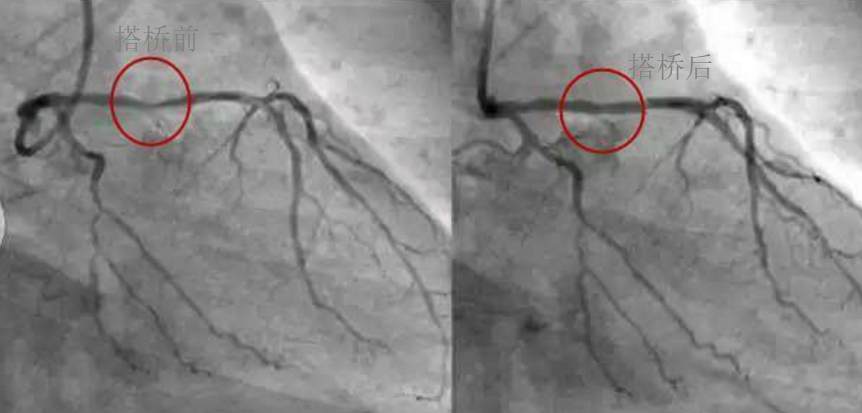

深圳市乐竞网页版入口厂对心脏支架的关注,国产化的道路有多长?

作为外科手术的医疗器材使用什么材料以及什么工艺制造的, 我们目前可以国产生产的设备和材料,